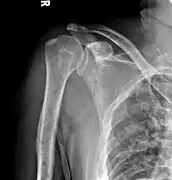

The diagnostic examination of a person with suspected multiple myeloma typically includes a skeletal survey. This is a series of X-rays of the skull, axial skeleton, and proximal long bones. Myeloma activity sometimes appears as "lytic lesions" (with local disappearance of normal bone due to resorption). And on the skull X-ray as "punched-out lesions" (pepper-pot skull). Lesions may also be sclerotic, which is seen as radiodense.[47] Overall, the radiodensity of myeloma is between −30 and 120 Hounsfield units (HU).[48] Magnetic resonance imaging is more sensitive than simple X-rays in the detection of lytic lesions, and may supersede a skeletal survey, especially when vertebral disease is suspected. Occasionally, a CT scan is performed to measure the size of soft-tissue plasmacytomas. Bone scans are typically not of any additional value in the workup of people with myeloma (no new bone formation; lytic lesions not well visualized on bone scan).

X-ray of the forearm, with lytic lesions